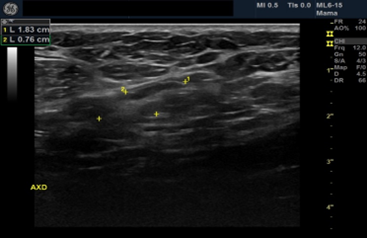

Female patient, black, 76 years old, G3P3, complaining of a lump in the right breast that had appeared 8 months ago. He has a history of admission to the intensive care unit 10 months ago due to an ischemic stroke, presenting left hemiparesis. Presents hypertension, hypothyroidism and dyslipidemia. Family history of father with prostate cancer. He presents sclerocalcification in the mitral and aortic valve on the echocardiogram. He presented clinical signs of an initial dementia process.Ultrasonography showed a heterogeneous image of 3.9/2.4/3.7cm in the union of the upper quadrants of the right breast, axillary lymph nodes with proportionality between cortex and hilum bilaterally BI-RADS 4 B BI-RADS 4 B.

On palpation, there was an 8cm nodule in the right breast and mobile and fibroelastic axillary lymph nodes. There were no palpable nodules in the cervical or supraclavicular region bilaterally. A core needle biopsy was performed with an anatomopathological result of triple-negative grade 2 adenoid cystic carcinoma. Staging demonstrated two 1.1cm pulmonary nodules with soft tissue density suggesting metastasis. Abdominal tomography demonstrated liver nodules suggestive of secondary implants. The PET scan confirmed uptake in the lung and liver nodules, in addition to lytic lesions in S3. Liver biopsy confirmed implantation of adenoid cystic carcinoma. The patient was staged as T2N0M1. Chemotherapy was started with a regimen of Carboplatin, Paclitaxel and Pembrolizumab. After the third cycle of chemotherapy, the breast was reevaluated without showing any tumor reduction. The metastases also did not regress, and treatment was interrupted. The patient evaded the service until he returned in January 2024 complaining of pain in his right hip and difficulty walking. Chest and hip tomography showed an increase in lung lesions and the appearance of lytic metastasis in the iliac bone (figure 1, 2, 3).

Figure 3: